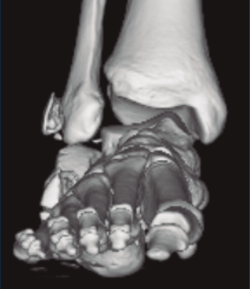

Se trata de un varón de 19 años que ingresa en reanimación tras precipitarse desde una altura de aproximadamente 10 metros. El paciente presenta una fractura estallido de L3 con afectación del canal medular junto con una fractura del vértice inferior de L4, así como una fractura luxación de calcáneo, asociada a una fractura del maléolo peroneo y del maléolo tibial posterior (Figuras 1 a 6) diagnosticadas mediante TC total body (por eso no se dispone de radiografías simples al momento del ingreso). Como podemos comprobar, se trata de una fractura de doble trazo de tipo hundimiento/depresión de la carilla articular (Figuras 5 y 6).

Figura 4. Luxación fragmento posterolateral.

Figura 5. Fractura maléolo peroneo, luxación astrágalo, fractura de doble trazo en calcáneo.

Figura 6. Fractura de doble trazo; se evidencia afectación de la articulación calcaneocuboidea.